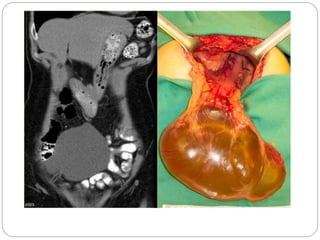

Pancreatic pseudocyst Large septated cystic mass in the mid abdomen with

nodular component. In the absence of history of pancreatitis it would be

difficult to differentiate this from a cystic pancreatic tumour.

• 27.

Mesenteric cyst. CT demonstratinga large left-sided cystic abdominal mass with compression of the left kidney. Ultrasound showed multiple fine septations within the cyst

Lymphangioma has enhancingsepta. Unlike in cystic peritoneal metastases, ascites is not a feature of lymphangioma. When you see a septated cystic lesion without ascites the most likely diagnosis is a lymphangioma

 Notice thatCT does not always appreciate the septations, although the specimen clearly shows multiple septations.